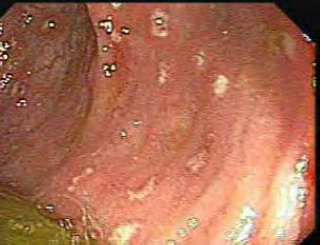

Tendo em vista esse caso clínico, a imagem apresentada e os conhecimentos médicos correlatos, julgue o item a seguir.